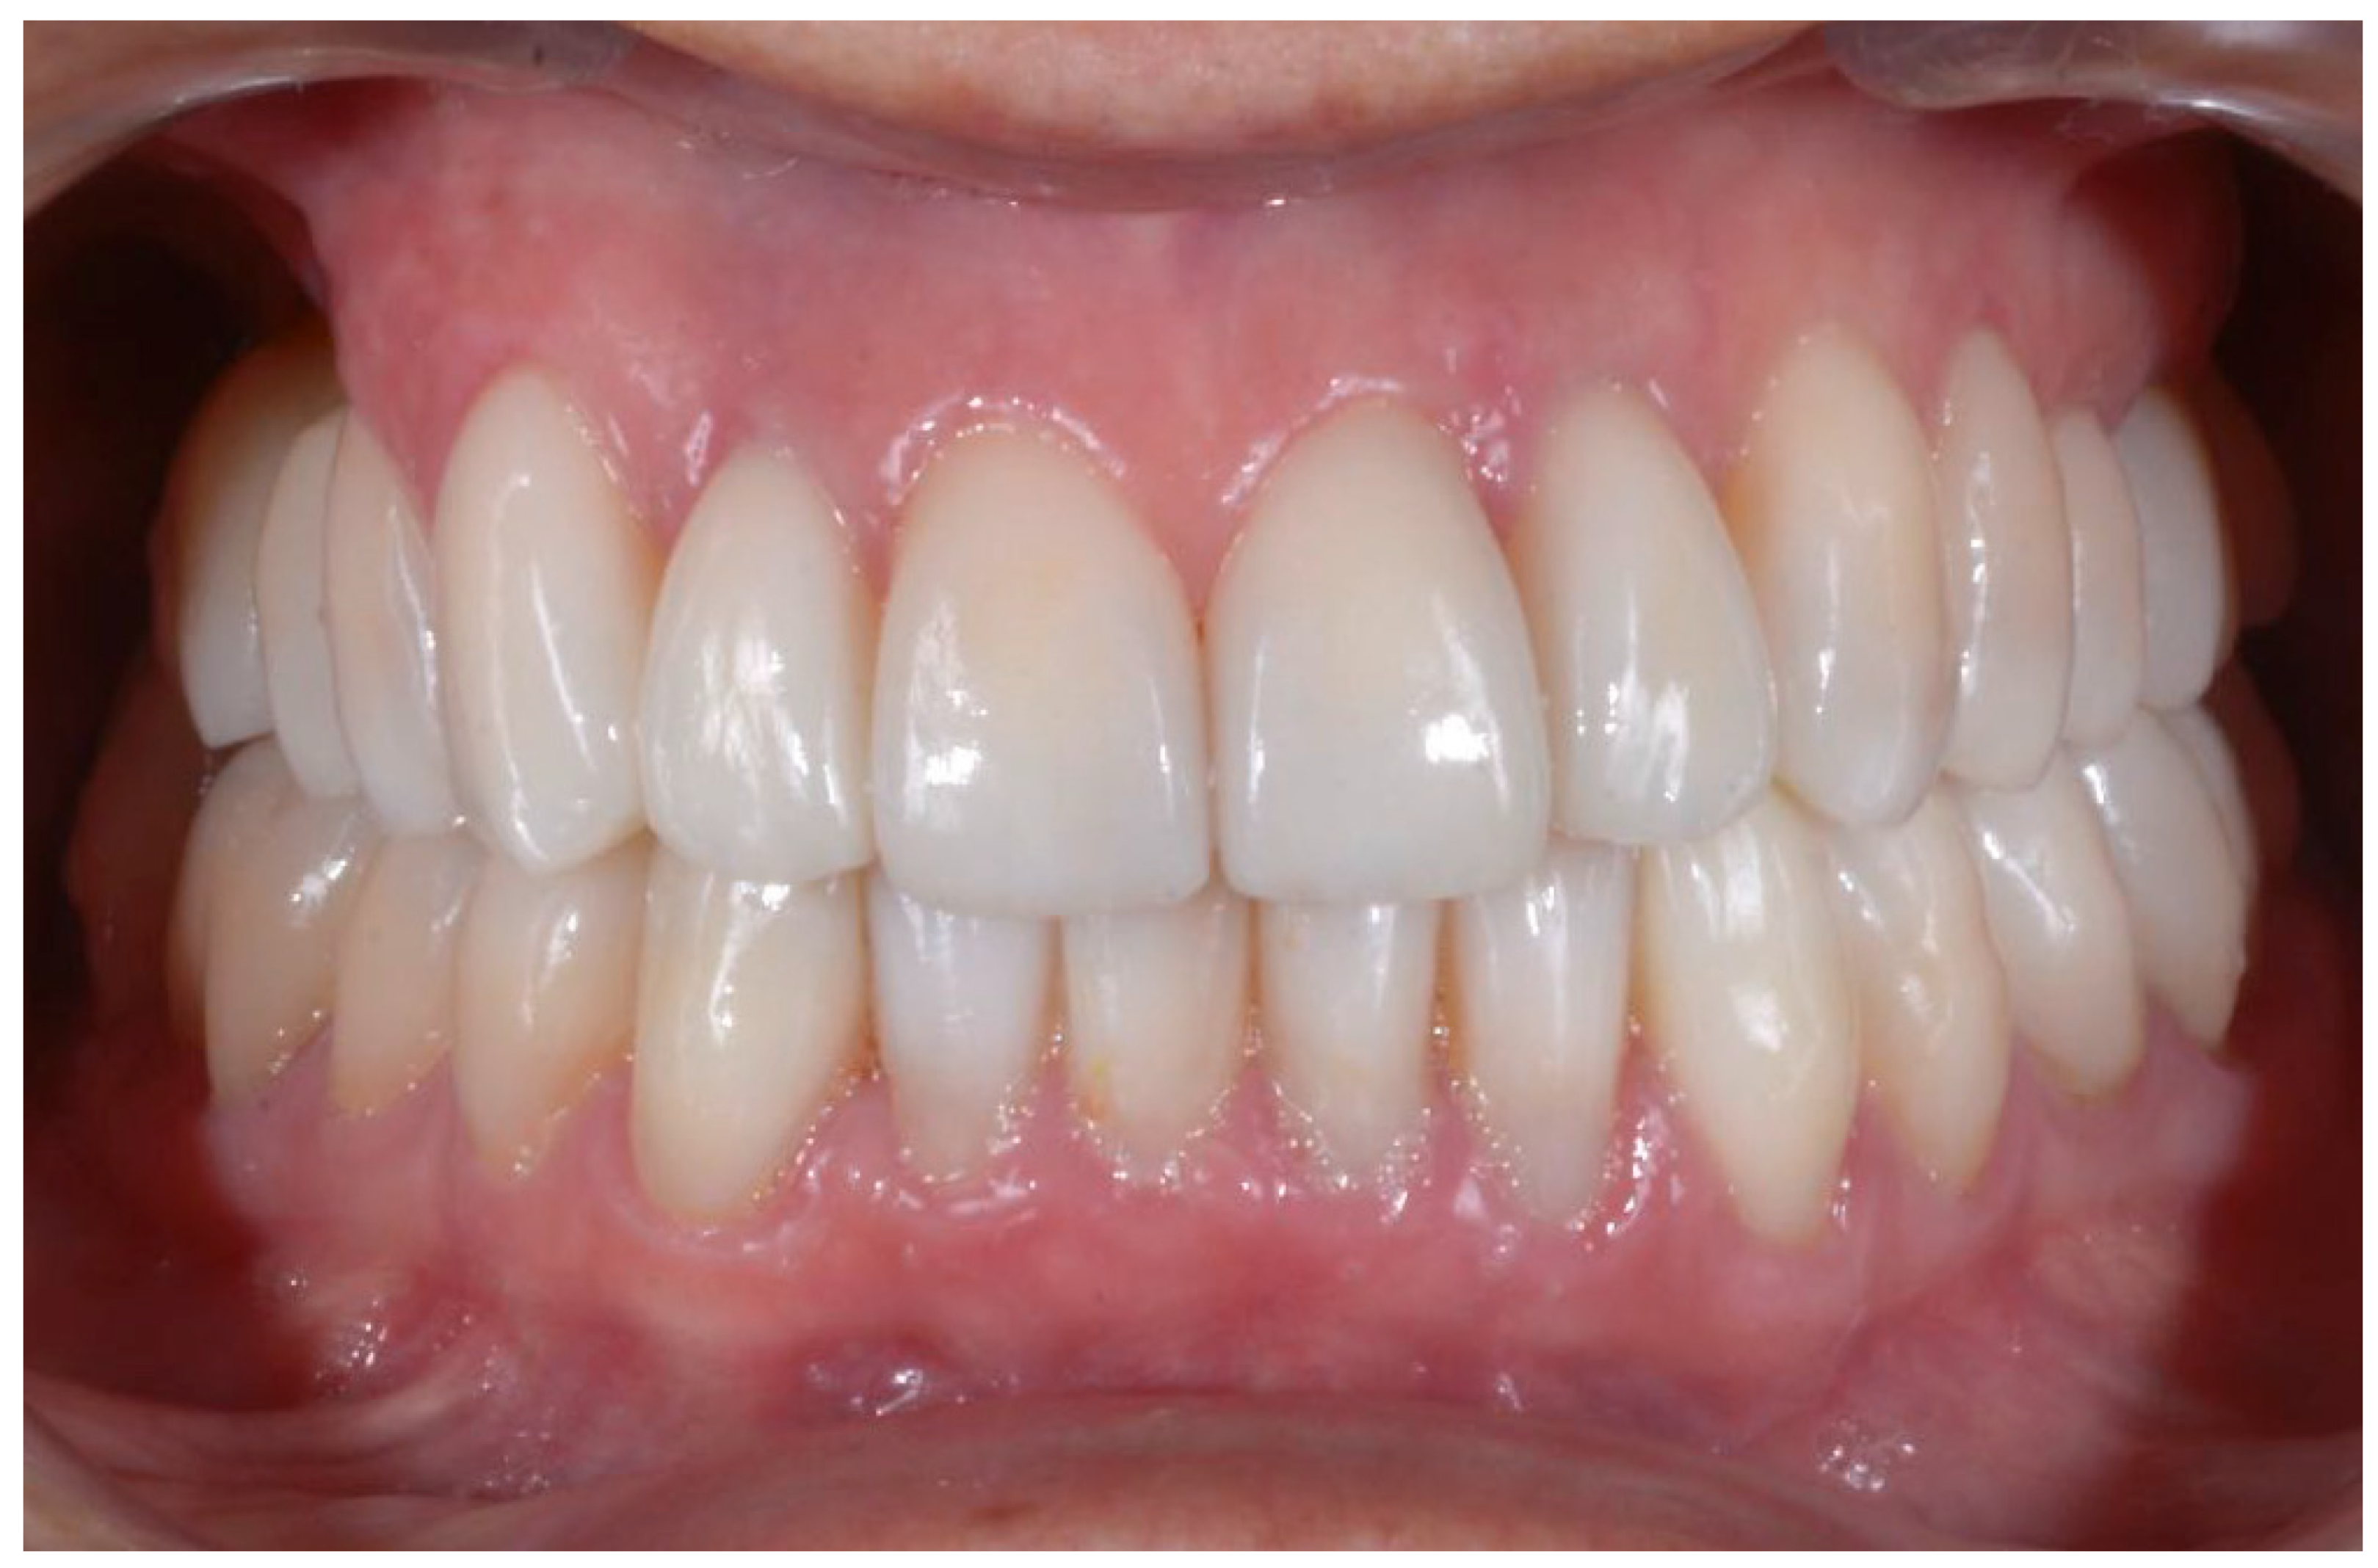

2.2. Clinical Example

2.3. Outcome Achieved

| Disharmonious smile | Yes | No |

| Dyschromia, dysmorphia, abrasions, and erosions of teeth | Yes | No |

| Anterior crowding in the upper arch | Yes | No |

| Anterior crowding in the lower arch | Yes | No |

| Upper transverse discrepancy | Yes | No |

| Presence of buccal corridors or black tunnels | Yes | No |

| Curve of Spee alteration | Yes | No |

| Curve of Wilson alteration | Yes | No |

| Functional movements with altered guides | Yes | No |

| Pain and/or noise ATM | Yes | No |

| Smile symmetry | Smile symmetry refers to the mirror agreement between the two sides of the mouth but can also consider the bi-pupillary line, the incisal line, and the labial commissure. | YES |

| Horizontal symmetry | It originates from the presence of similar elements placed in a regular sequence, as verified in a dentition with teeth well aligned in the horizontal plane. | YES |

| Vertical symmetry | Recall the same principle as above, referring to the vertical direction. | YES |

| Repeated report | It indicates the division of space into portions that may not be identical in shape and size but arranged to generate a harmonious connection between them. This is what is verified between opposing hemiarches with well-arranged teeth, inspiring a sense of order and balance. | YES |

| Prospective effect | The contour of the buccal surface and the alignment of the inclined planes of the teeth is decisive in generating a correct perspective effect. The different length or strong color difference of even one element can impair the perspective effect and compromise the sense of harmony of the whole. | YES |

| Lip height | Useful distinction in static and dynamic harmony. The average height of the upper vermilion is 7.1 mm in the male and 7.7 mm in the female. The lower vermilion is normally more extensive, about 10 mm on average; these are statistical values, with wide individual variations. | YES |

| Lip line | The height of the upper lip, relative to the upper central incisors, can be classified as low, medium, or high, on the basis of the amount of crown exposure. | YES |

| Smile line | Smile line is a curved line passing through the incisal margin of the upper incisors, parallel to the inner margin of the lower lip. | YES |

| Curvature of the upper lip | With superior convexity, it extends from the center toward the lateral triangular spaces. When rectilinear or worse with inverted convexity, it gives the subject a sad and unattractive expression. | YES |

| Frontal axial alignment | The smooth slope of the long axis of the front elements helps generate a sense of regularity. | YES |

| Tooth alignment in the arch | Recalls the anatomical harmony represented by the correct positioning of teeth in the center of the alveolar ridge. | YES |

| Contact point alignment | In the anterior sectors, the contact points are located near the incisal third and their sequence defines a curvilinear pattern. | YES |

| Color | Color is one of the cardinal elements of dental aesthetic recovery. It must always be evaluated in a much broader context, involving many other periodontal, labial, and skin parameters of the patient. | YES |

| Gingival scalloping | Gingival parabolas are decisive for the aesthetic effect of the frontal group. Orthodontic treatment can contribute to their harmonization. | YES |

| Negative space | A restrained smile enhances the characteristics of the teeth, while an excessive smile imparts an unattractive sense of emptiness. | YES |

| Arch geometry | There are several types of arch form related to individual craniofacial conformation that must be recreated or respected by orthodontic treatment. | YES |

| Buccal corridors o black tunnels | A restrained smile enhances the characteristics of the teeth, while an excessive smile imparts an unattractive sense of emptiness. | YES |

| Fibonacci golden proportion | It evaluates proportions by relating harmony to numerical values. In the dental field, it can find application in the evaluation of various dental and facial morphological parameters. | YES |